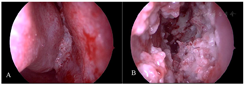

患者入院查体:体温37.8℃,脉搏78次/分,呼吸18次/分,血压126/81mmHg,神志清,精神差,发育正常,营养良好。全身皮肤黏膜无黄染,浅表淋巴结未触及肿大,双肺呼吸音清,心音有力,心率78次/分,心律齐,腹软,全腹无压痛、反跳痛,肝脾肋下未及,肾区无叩痛,肠鸣音正常,双下肢不肿。肛周手术切开创面,局部水肿,可见少许脓血性分泌物。专科查体见鼻背略增宽,鼻内镜检查见左侧鼻腔黏膜弥漫性坏死,伴血水样分泌物(图1A),右侧鼻腔鼻中隔后部穿孔(图1B)。左上列牙齿疼痛,上颌窦前壁压痛,鼻背部未触及压痛。右耳后可见脓肿,已破溃结痂,周围皮肤略充血,咽喉部未见明显异常。

既往文献表明,在合并头颈部表现的GPA患者中,鼻部为最常见的受累部位[3],部分患者甚至可以鼻部症状为唯一表现[2]。鼻堵是常常是GPA患者鼻部受累时的首发症状,当鼻粘膜的炎症继续进展时,可逐渐出现嗅觉下降,合并细菌感染后可出现鼻腔异味[4]。以上症状在临床上并无明显特异性,与急性鼻窦炎极容易混淆,正如本例患者在发病初期表现为鼻塞、脓涕、头痛等急性鼻窦炎症状,先后于外院及我院门诊按照急性鼻窦炎进行诊断和治疗。但GPA与急性鼻窦炎又存在显著的差异,GPA疾病活动期的鼻部症状主要表现为鼻腔结痂,伴有鼻腔血性分泌物、鼻部疼痛和嗅觉丧失,鼻腔黏膜在鼻内镜下表现为炎症肿胀、质脆,伴溃疡或肉芽肿形成[5],常规抗感染治疗无效,部分患者在就诊时可有骨或软骨的破坏,表现为CT上的骨质侵蚀或鼻中隔穿孔。本例患者在经过常规鼻窦炎药物治疗2个月症状无显著改善,后续患者逐渐出现了鼻腔血性分泌物及肺部结节、发热咳嗽症状,鼻内镜下黏膜大面积溃疡、质地脆,提示患者诊断并非急性鼻窦炎。因此,在面对临床症状符合急性鼻窦炎,但抗感染治疗无效的患者时,需注意患者的全身症状,进行更全面的检查。